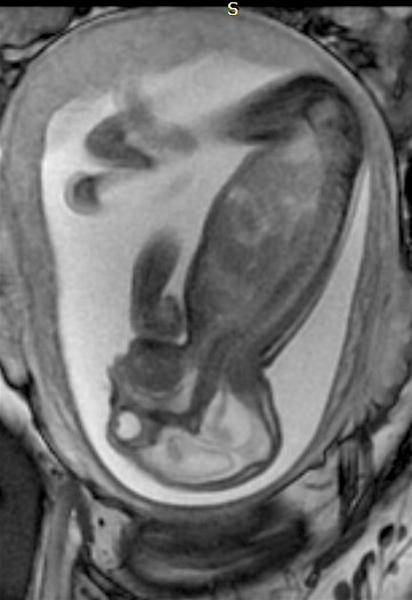

The rapid spread of Zika virus in the Western Hemisphere this past year has caused great alarm in the United States ...